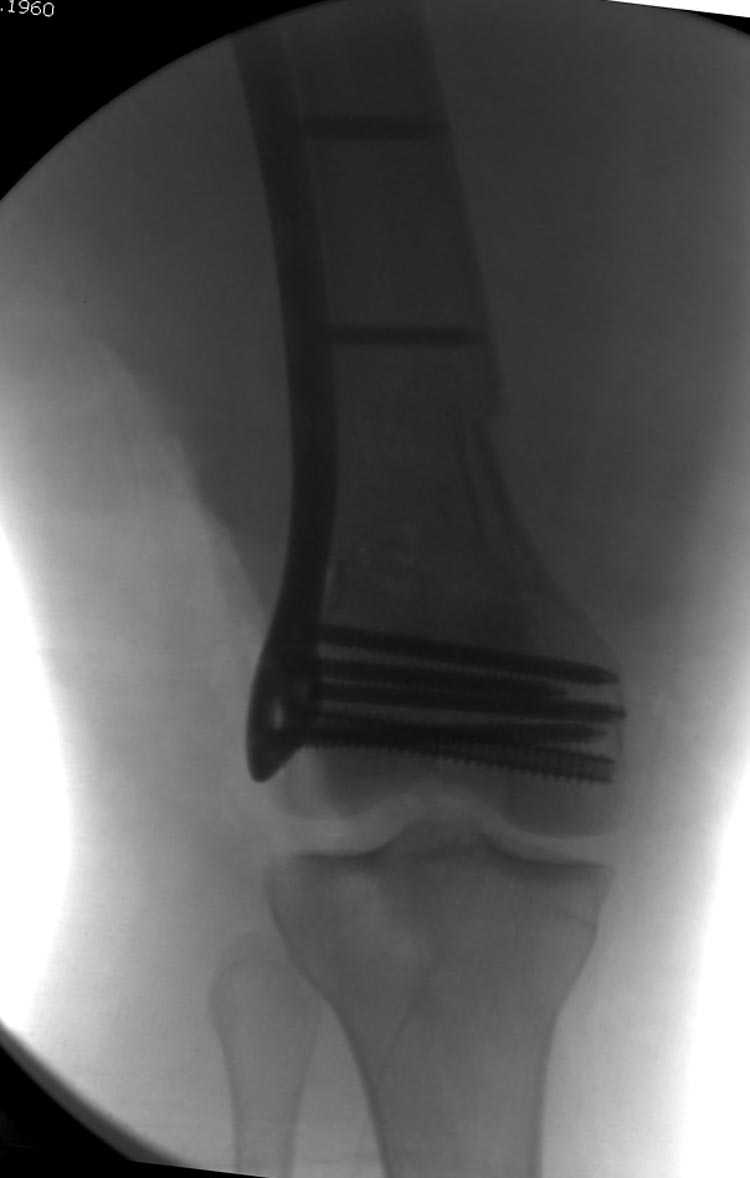

Бесспорно, предлагаемый ретроградный метод имеет свои преимущества, но имеется опасность при манипуляции интрамедуллярным гвоздем расколоть мыщелки.

Раскол можно предупредить шурупами, но короткий дистальный фрагмент навряд ли позволит добиться адекватной стабильности конструкции. Стандартные гвозди не рассчитаны для таких переломов, и если все таки желаете провести фиксацию гвоздем, тогда надо заказывать специальный custom made nail т.е. с расширенной возможностью дистальной блокировки.

Почти все компании имеют пластины с угловой стабильностью, начиная от Stryker, Zimmer NCB и DePuy Polyaxial Plate . Если у NCB шуруп блокируется специальной шайбой, то Polyaxial Plate имеет вариабельный угол введения шурупов.

Поэтому такие меж и над- мыщелковые переломы более предпочтительным считается фиксировать мыщелковыми пластинами

Устанавливается из малого разреза "не вскрывая сустав" со стороны латерального мыщелка, и Insertion Jig позволяет установить пластину "мостовидно" перкутанно в проксимальном отделе, "не вскрывая и не трогая" место перелома.